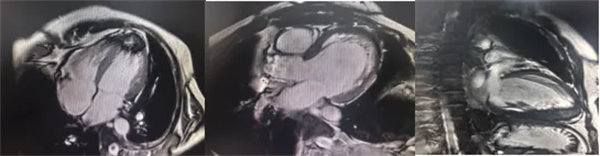

在常規(guī)心臟MRI檢查中,醫(yī)學(xué)影像科發(fā)現(xiàn)患者心肌異常表現(xiàn),考慮鐵過(guò)載性心肌病,為明確診斷要進(jìn)一步加做鐵定量技術(shù),加掃T2 mapping序列。CMR鐵定量技術(shù)是目前評(píng)估心肌鐵含量的“金標(biāo)準(zhǔn)”,能夠快速、無(wú)創(chuàng)、精準(zhǔn)量化心肌內(nèi)鐵沉積程度,檢查結(jié)果提示患者局部心肌T2*值顯著低于正常范圍,符合鐵過(guò)載性心肌病的診斷標(biāo)準(zhǔn)。

基底部、中間部及心尖部 局部心肌T2*值明顯減低T2* 10-20/s, 部分小于10/s

心肌信號(hào)局部減低 呈現(xiàn)“黑色心肌”表現(xiàn),這是由于鐵沉積導(dǎo)致局部磁場(chǎng)不均勻,引起信號(hào)丟失(失相位)。